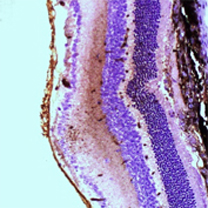

Ocular Histopathology and Immunohistochemistry

- GLP histopathology for ocular toxicology studies: ocular examination of globe and adenexal structures

- Histopathologic examination of ocular tissues from research studies

- Ocular pharmacology models

- Ocular immunohistochemistry

Histology Images